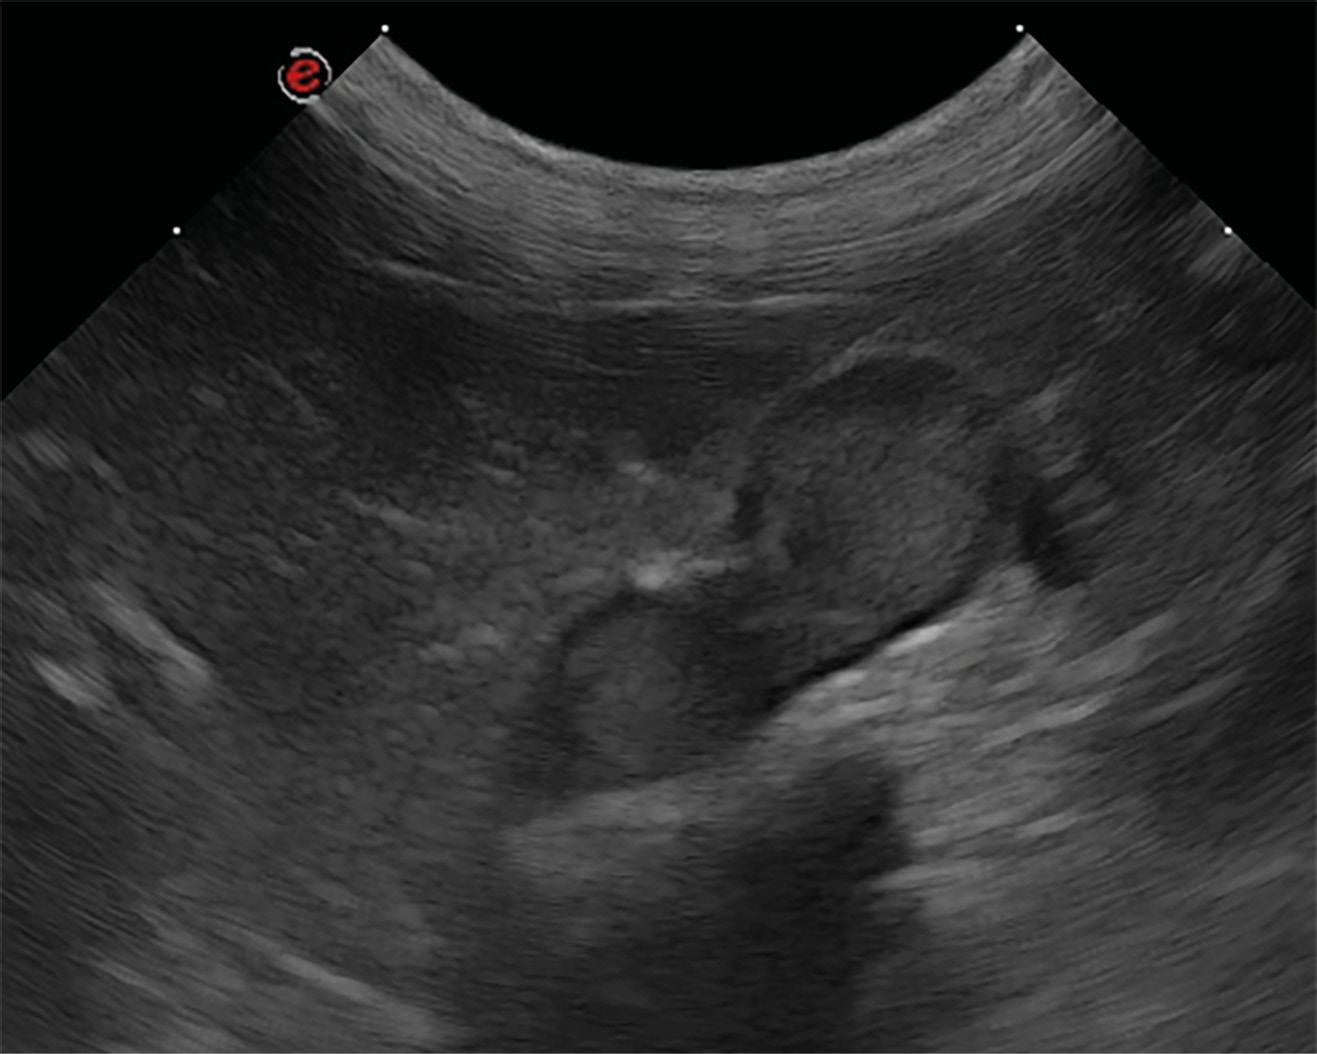

El diagnóstico diferencial de nódulos y masas adrenales incluye hiperplasia adrenal, adenoma, adenocarcinoma, feocromocitoma y, con menor frecuencia, aunque también se han reportado: neuroblastoma, ganglioneuroma, mielolipoma, metástasis, granuloma, hematoma21. Ecográficamente no se puede diferenciar un tumor maligno de uno benigno, pero la presencia de una masa igual o superior a 2 cm de tamaño y/o la observación de invasión vascular deben considerarse criterios de malignidad22 (imágenes 3 y 4).

La ecografía también permite esta toma de muestras mediante punción ecoguiada con aguja fina. La seguridad de esta técnica fue estudiada por Sumner et al., 2018, que determinó que es relativamente segura y la considera parte del algoritmo diagnóstico en la investigación de una lesión en la glándula adrenal27.